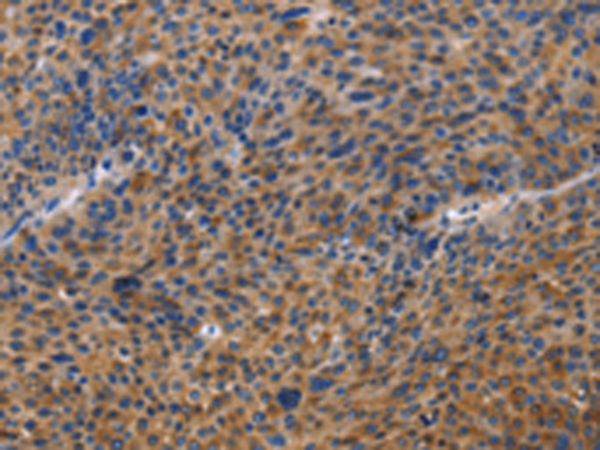

分类: 科研抗体货号: P07970别名: IDH; IDP; IDCD; IDPC; PICD应用: WB,IHC反应种属: Human, Mouse, Rat